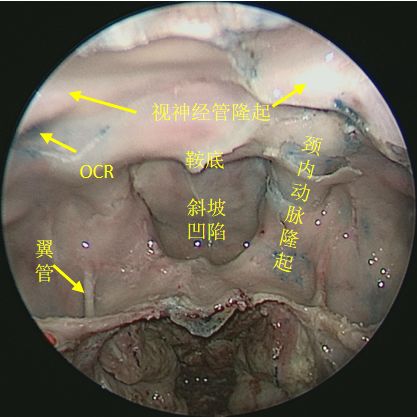

开放蝶窦前壁,观察蝶窦内骨性隆起 ↓

↑ 抵近离观察蝶窦内骨性隆起及凹陷